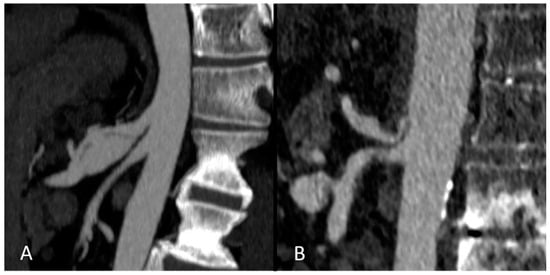

- Lin, T.-S.; Chiang, Y.-C.; Chen, C.-L.; Concejero, A.M.; Cheng, Y.-F.; Wang, C.-C.; Wang, S.-H.; Liu, Y.-W.; Yang, C.-H.; Yong, C.-C. Intimal dissection of the hepatic artery following transarterial embolization for hepatocellular carcinoma: An intraoperative problem in adult living donor liver transplantation. Liver Transplant. Off. Publ. Am. Assoc. Study Liver Dis. Int. Liver Transplant. Soc. 2009, 15, 1553–1556. [Google Scholar] [CrossRef] [PubMed]